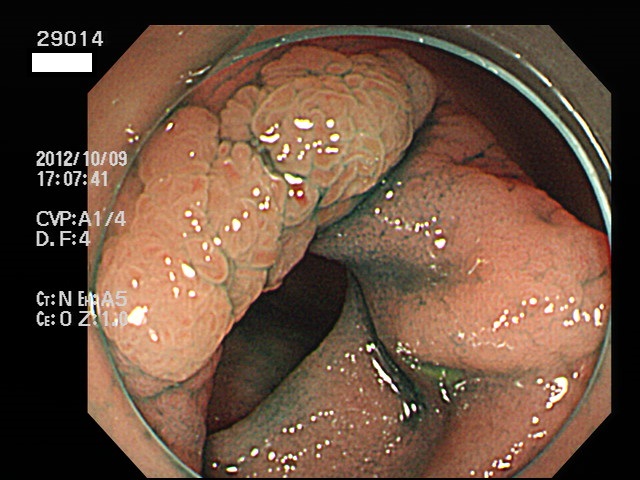

回盲弁(小腸と盲腸の境界)や、憩室の中、炎症で腫れた部位などは複雑に凸凹しており、ここに微小な病変、平坦な病変があると認識が困難になり見落としの危険が高くなります

| 炎症性の隆起(腫れ)の上に発生した腺腫 | 回盲弁上に発生した腺腫(高度異型) |